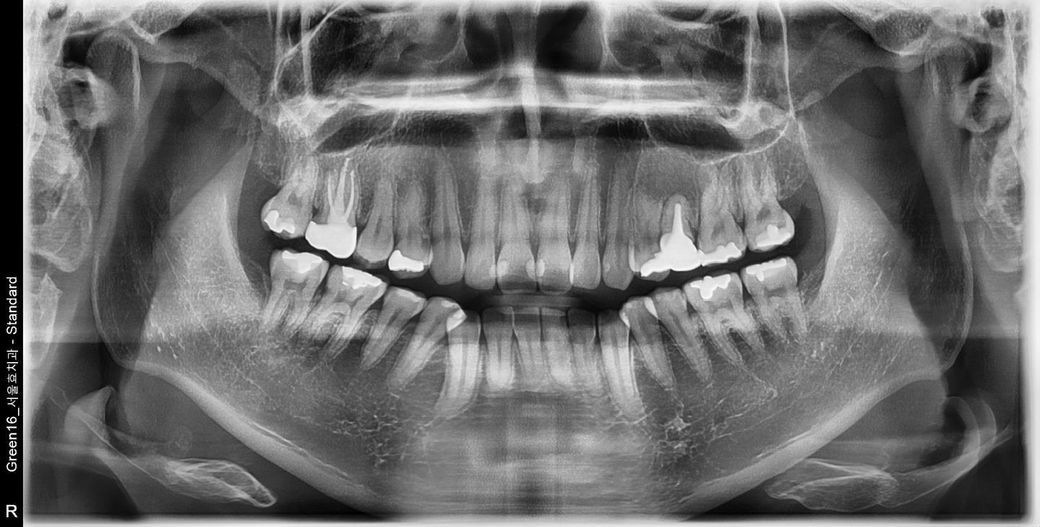

오른쪽 아래 매복 사랑니 발치 후 어금니 뒤 잇몸에 이상한 작은 혹 같은 게 생기고 통증이 있는데 크기가 점점 커지는데 이게 원인이 무엇일까요? 치과에 가니까 그냥 뭐 잇몸이 씹혀서 그렇다 괜찮다 이러는데 통증도 심하고 크기도 커지고 원인인 뭔지 원래 사랑니 발치 후 1년 지난 시점부터 생겨서 종양이나 암이나 안 좋은 질환일 수도있나요? 사진이랑 파노라마 사진 첨부합니다

잇몸이 자라면서 해당부위 과증식된 것이 아닐까 싶습니다 특별히 엑스레이상으로는 문제가 없어보입니다